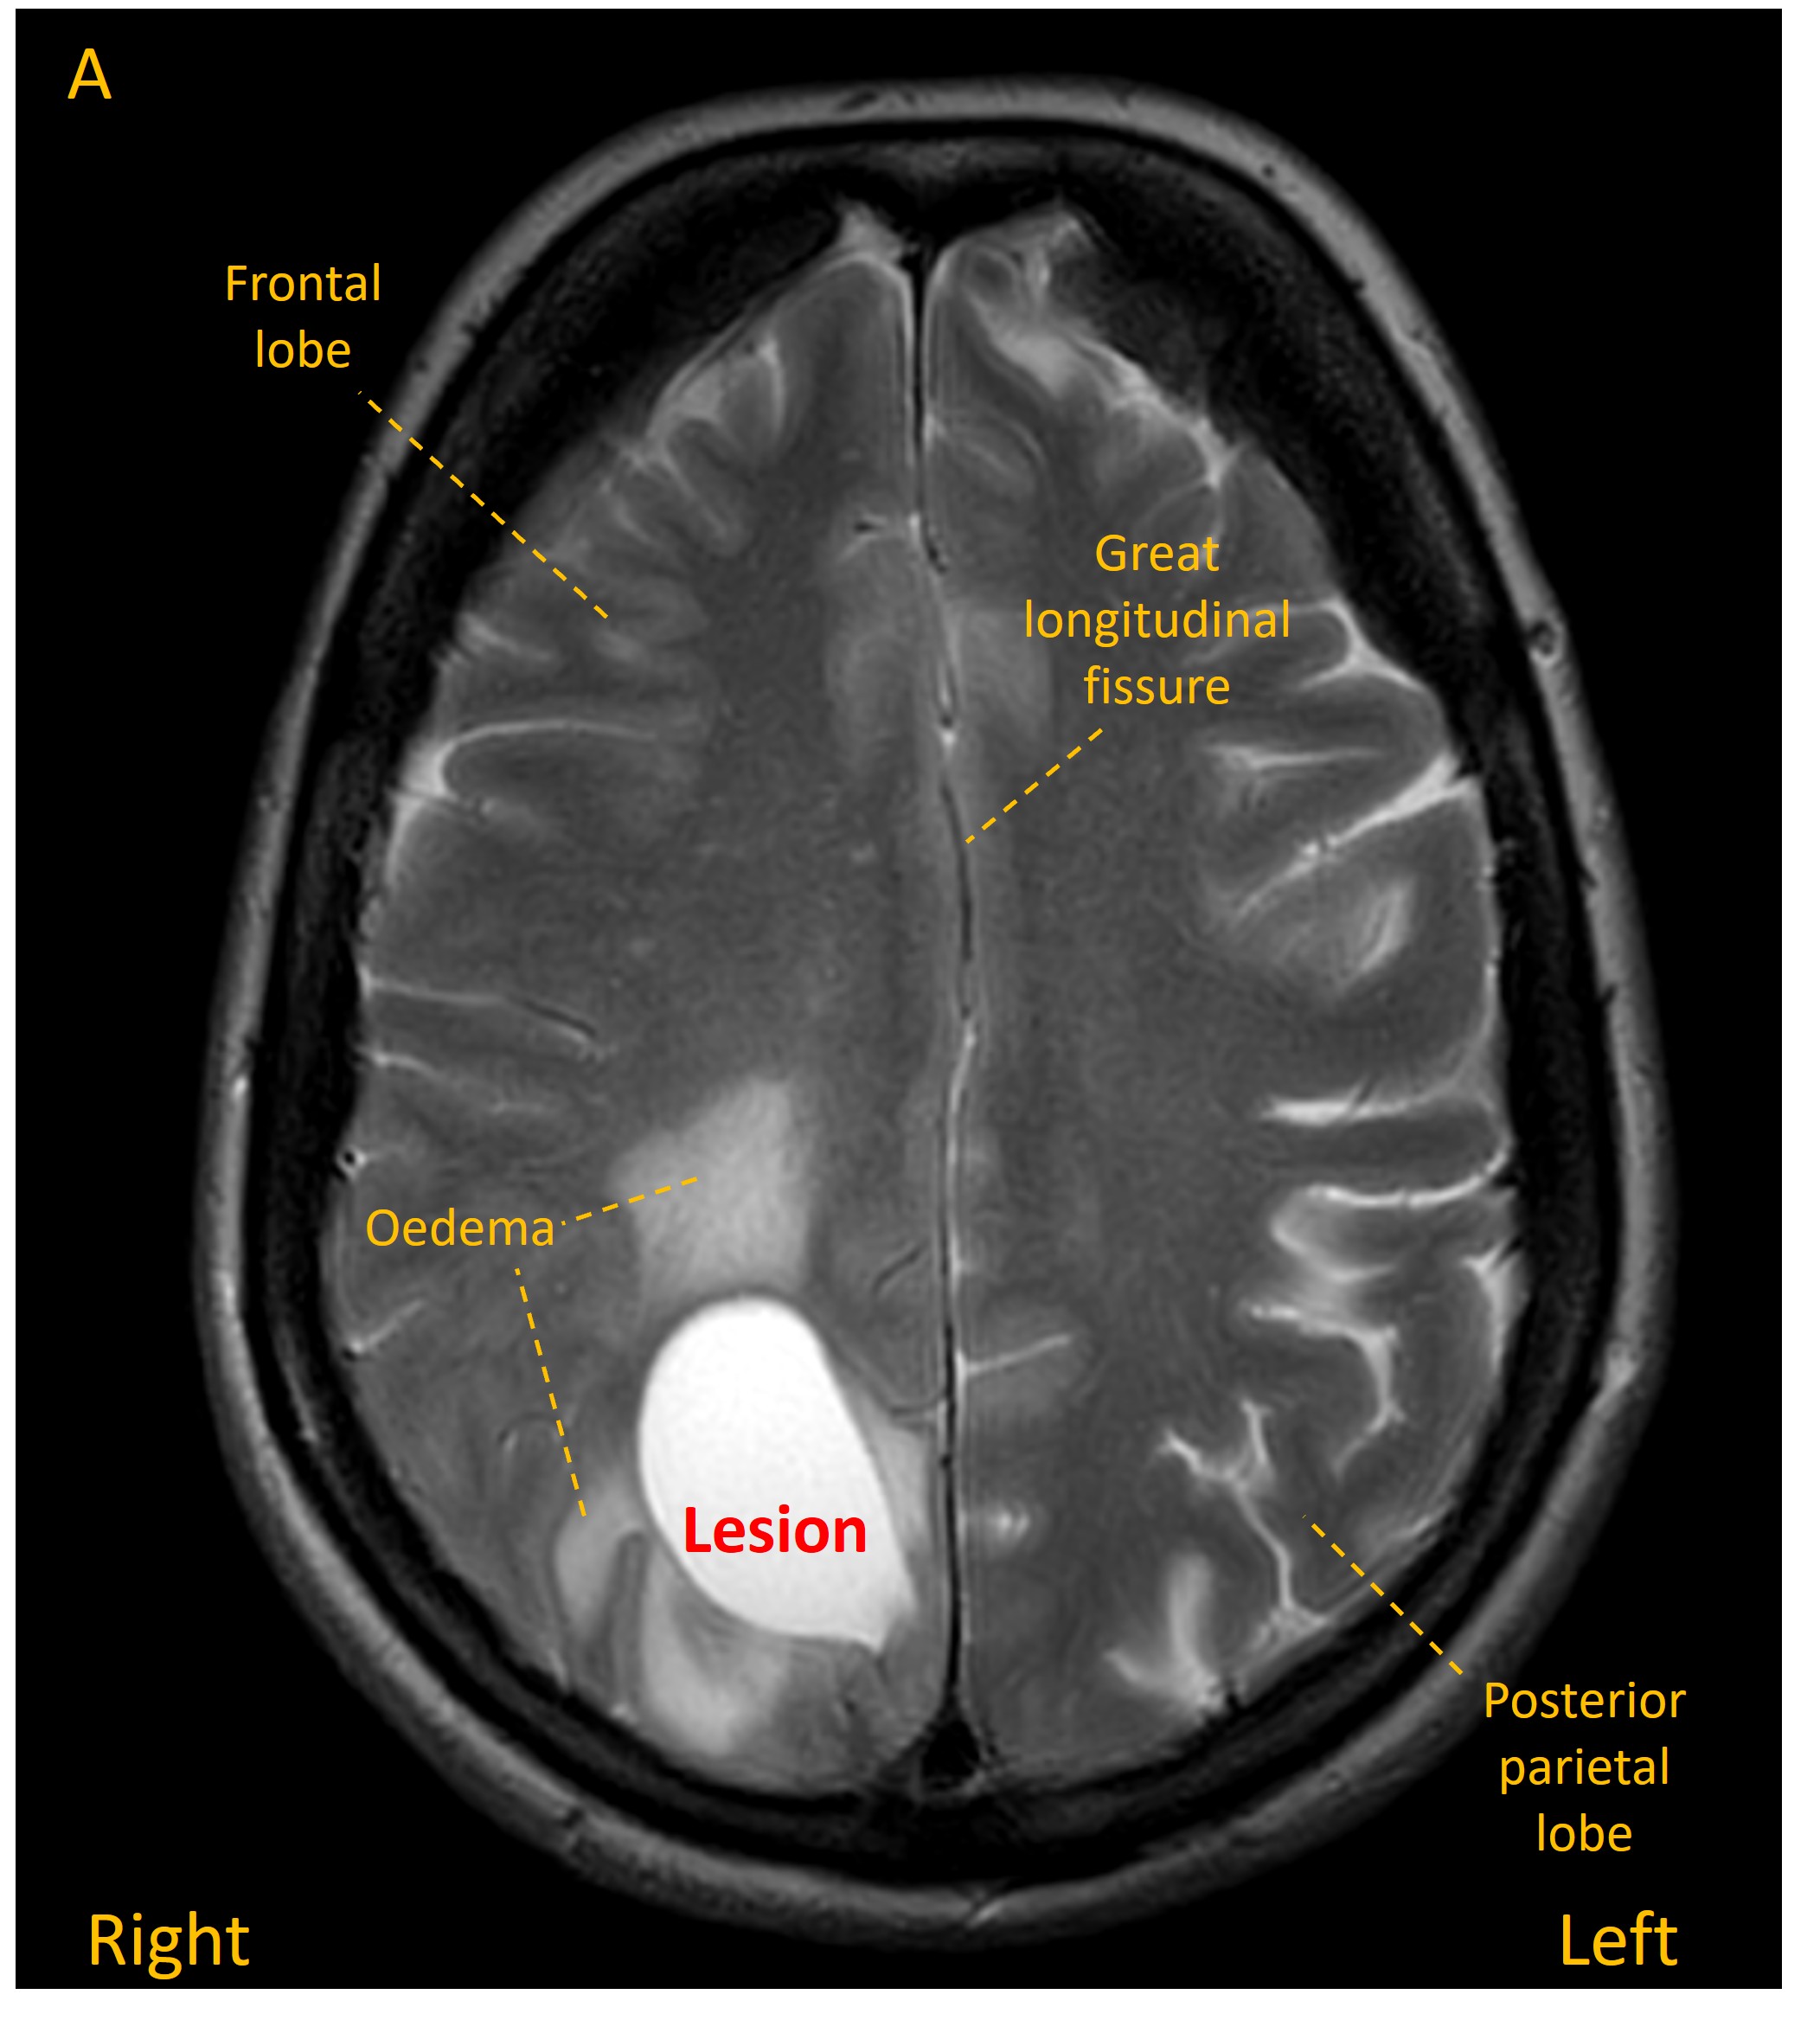

An MRI revealed a mass in the right parietal lobe with a solid component and a deeper cyst, associated with some white matter oedema and some sulcal effacement (images A-C).

MRI 2